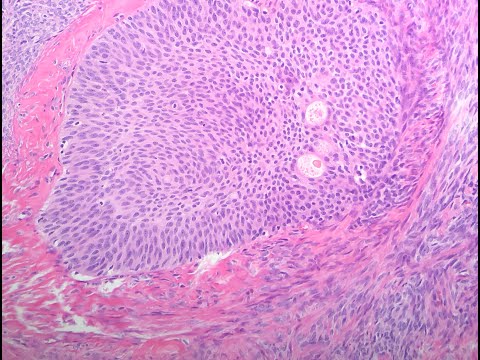

Lesson 5, Part 2: Epithelial Tumors of the Ovary

To understand the basic classification of epithelial ovarian tumors and to recognize pertinent features on histology.